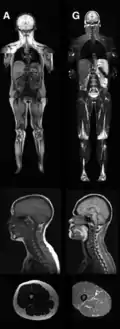

![]() MRI of control patient vs. diseased patient. تصوير بالرنين المغناطيسي يوضح فقدان دهن تحت الجلد عند شخص مصاب بالمرض (G) مقارنة بشخص اعتيادي (A). | |